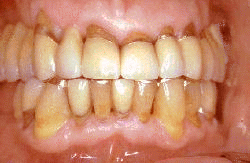

El mismo paciente después del tratamiento, la patología periodontal se ha eliminado y las profundidades de bolsa son de 1-2 mm.  La condición periodontal se observó durante tres citas en un mes. La salud periodontal se mantuvo por los procedimientos de higiene oral y la rehabilitación protética del maxilar superior.

Después de  3 años del tratamiento periodontal y rehabilitación oral por puentes fijos. La condición periodontal es estable y el nivel de higiene oral se mantuvo. El puente fue diseñado para permitir una  limpieza eficaz de las raíces y las uniones entre las raíces y las coronas. Note en particular el ancho espacio interdental y el ajuste de las coronas a la anatomía de superficie de la raíz. El paciente es recitado cada seis mes y no se observó ninguna progresión a enfermedad periodontal.